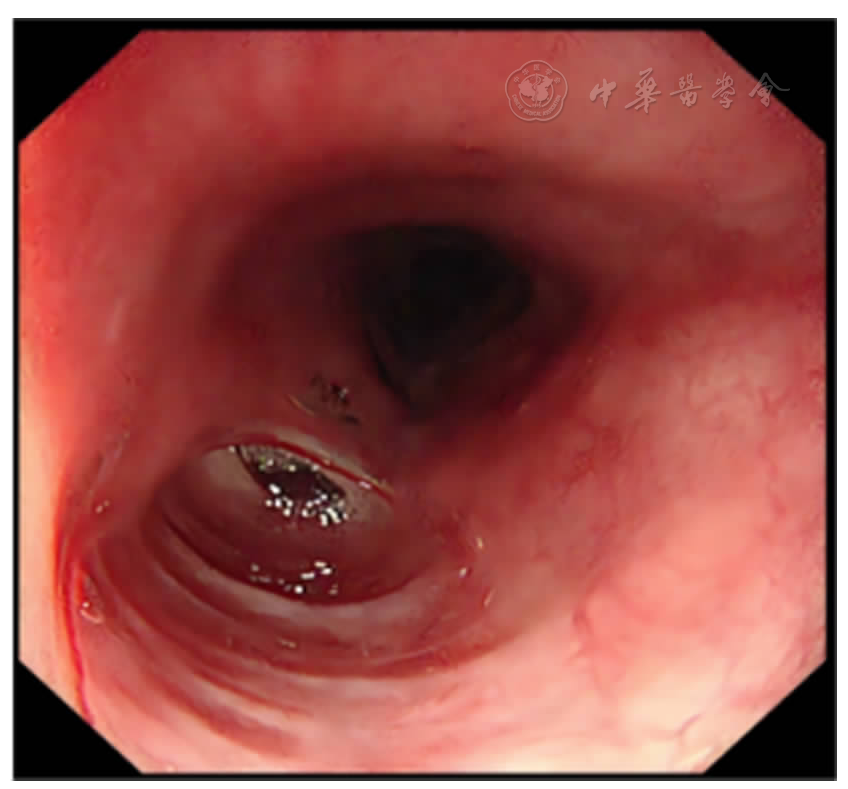

图1 第一次胃镜检查:左侧咽部可见一隆起性病变,右侧食管入口处似可见脓性分泌物,内镜无法通过(2024-9-17)

图2 第二次胃镜检查:小儿内镜可经较大的黏膜缺损进入黏膜下层,其内可见多发分隔(2024-10-18)